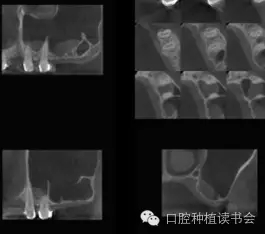

總結(jié)上頜竇腔的骨性結(jié)構(gòu)特點,人們發(fā)現(xiàn)上頜竇底并一定是平坦的,有些竇底會有斜坡狀的情況(圖3)。而上頜竇的分隔情況發(fā)生率可達上頜竇數(shù)量的27.7%,病人數(shù)量的37%。分隔在上頜竇前部占22.5%,中部占45.9%,后部占31.5%(Park,2011)(圖4)。所以SFE的障礙之一就是骨性結(jié)構(gòu)的變異,給提升技術(shù)和工具帶來挑戰(zhàn)。

▲(圖3)

▲(圖4)